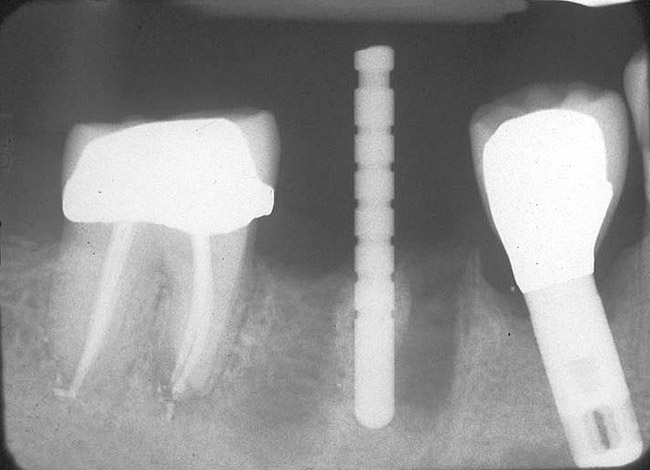

If the most crestal aspect of the interradicular bone is at least 3-mm-wide mesio-distally: A 2.2-mm-wide guide bur is drilled to the appropriate length, a guide pin is inserted, and a radiograph is taken (Figure 7). If necessary, the initial osteotomy is extended apically. A tapered osteotome is inserted into the osteotomy and moved mesio-distally and bucco-lingually to expand the osteotomy site. A 2.8-mm bur is used to prepare the osteotomy to depth, and a 2.8-mm-wide tapered osteotome is inserted in the osteotomy and once again utilized in mesio-distal and bucco-lingual directions to expand the osteotomy site. If the mesial and distal aspects of the interradicular bone are still intact at this point, a 3.5-mm bur is utilized to prepare the osteotomy to depth. A 3.5-mm-wide osteotome is inserted into the osteotomy and utilized in the manner already described. A decision is made as to whether to place a tapered implant with a 4.1-mm-wide base and a 6.5-mm-wide neck, or to use a 4.8-mm-wide bur and prepare the osteotomy to depth, in anticipation of placement of an implant with a 4.8-mm-wide parallel wall body and a 6.5-mm-wide platform. The chosen implant is inserted into the osteotomy (Figure 8), appropriate regenerative materials are placed, and the flaps are sutured. Following maturation of the regenerating hard tissues, the implant is ready for restoration (Figure 9). A radiograph taken 54 months after implant restoration demonstrates stability of the peri-implant crestal bone (Figure 10).